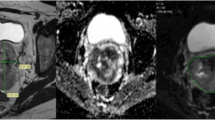

ADC maps were generated using a monoexponential decay model with b value of 0 and 1,000 s/mm2 (VB17a, Trio TIM; Siemens Healthineers). Anonymous data were exported offline to a personal computer. By using an in-house developed software based on Matlab (MathWorks, Natick, MA, USA), the first reader (Y.T.H, a gynaecological radiologist with 8 years of experience) drew regions of interest (ROIs) around the tumour on each slice on the ADC maps with reference to the high b value DW and T2-weighted images to delineate the whole tumour volume to minimise the slice selection bias. The second reader independently verified the ROIs (G.L., a gynaecological radiologist with 10 years of experience). Both readers were blinded to clinical outcome. Care was taken to avoid non-pathological structures in the ROIs, such as normal cervical stroma, vascular structures, fluid or Nabothian cysts in the cervix. The mean, minimum, 10th, 25th, 50th, 75th and 90th percentiles and maximal pixel ADC values (ADCmean, ADCmin, ADC10, ADC25, ADC50, ADC75, ADC90 and ADCmax, respectively) were generated, and the skewness and kurtosis of the histogram were recorded (Fig. 2). The tumour volume was calculated by multiplying the voxel size of DW image by the number of voxels in the ROI, where the voxel size = in-plane pixel size (1.5625 mm2) × (4 mm slice thickness + 1 mm gap) = 7.8125 mm3.

Representative volumetric apparent diffusion coefficient (ADC) measurement. a Coloured scale bar, × 10-3 mm2/s. b Histogram analysis. A 47-year-old woman with moderately differentiated squamous cell carcinoma of uterine cervix, clinical stage T2b N0 M0, HPV genotype 18, maximal tumour diameter 7.3 cm, ADC10 0.68 × 10-3 mm2/s, ADC50 0.82 × 10-3 mm2/s (green), ADC90 1.00 × 10-3 mm2/s (red). This patient had persistent disease following concurrent chemoradiation therapy. Overall survival time, 8.1 months